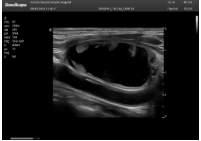

肥厚性心肌病-心尖四腔